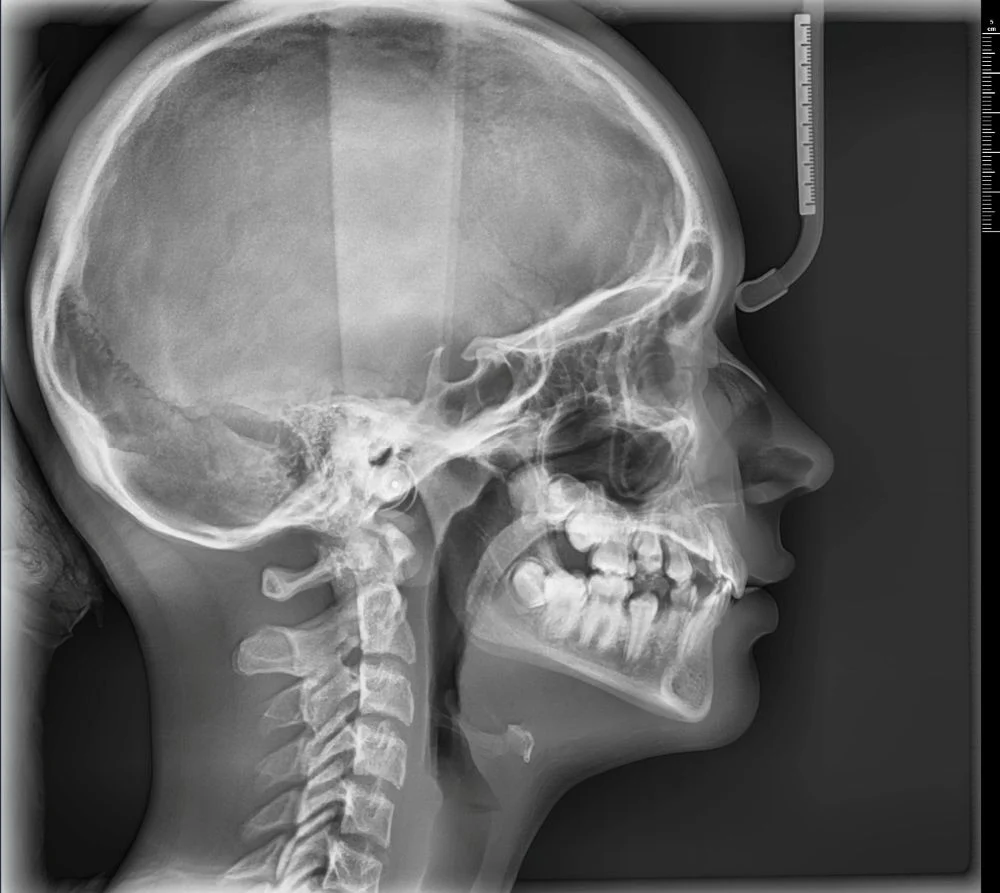

- wyraźne obrazy 2D i 3D — pomocne przy implantach, ósemkach, leczeniu kanałowym i ortodoncji

Pantomogram pokazuje cały stan uzębienia i kości — dzięki temu można wykryć zmiany, których nie widać na małym zdjęciu punktowym (jak torbiele, stany zapalne czy problemy ze stawami). To proste badanie, które warto wykonać profilaktycznie co kilka lat.

Tomografia CBCT tworzy trójwymiarowy obraz zębów, kości, zatok i stawów.